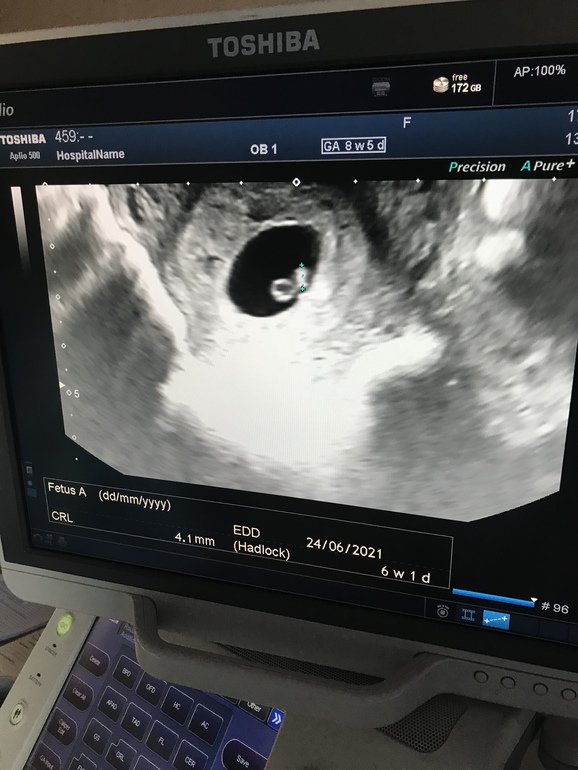

КТР 4.1 мм, срок по узи рисуется 6 недель 1 день, ПДР исходя из этого на 24.06.2021. По хгч примерно так и прикидывала) Расхождение с месячными больше 2 недель конечно.

А сейчас вот так :